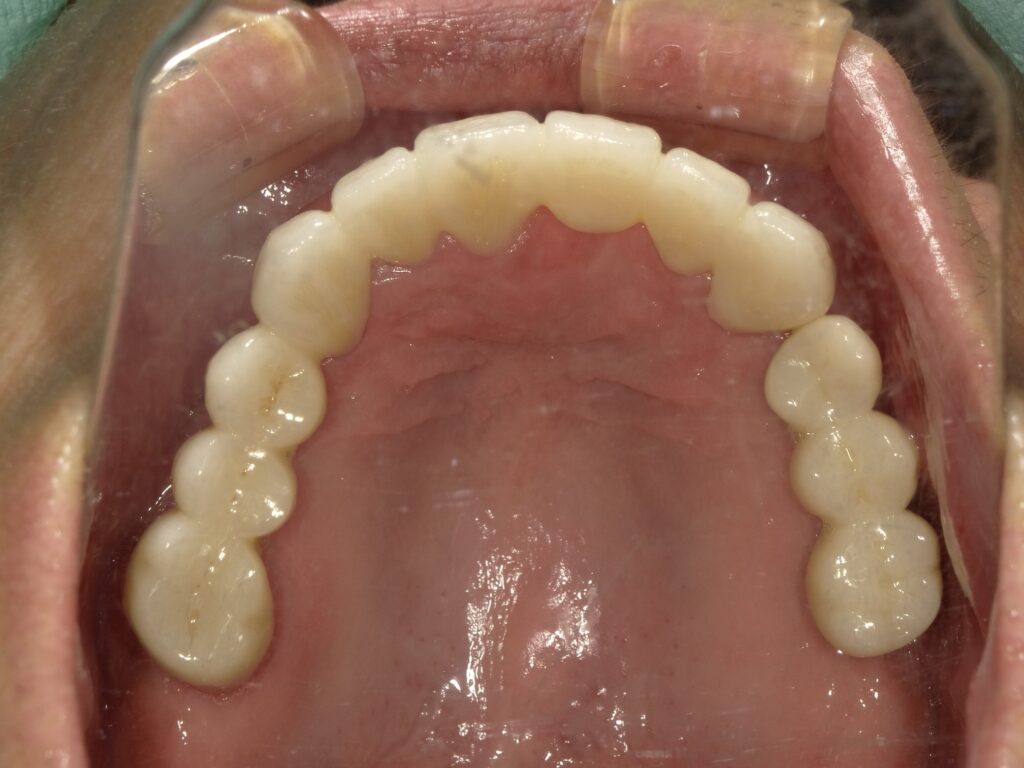

BEFORE

主訴

全体的に見た目を綺麗にしたい。奥歯でしっかり噛みたい。

診断名・主な症状

臼歯部欠損

年齢

65歳

治療内容

インプラント埋入(左下5・6,右下5・6,左上4・6)

サイナスリフト(左上4・6)

ジルコニアBr(右上6−左上3)

E –MAX CAD(右下4)

セラミックインレー(左下4)

治療期間/

通院回数

約1.5年/約20回

費用

インプラント治療 約2,000,000円

その他被せ物治療など 約1,000,000円

合計 約3,000,000円

*いずれも税込